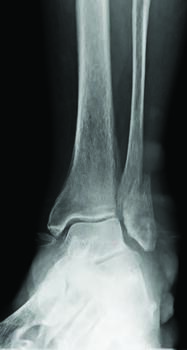

Ankle fractures are common orthopedic injuries, accounting for approximately 20 percent of lower extremity trauma.1 Of these fractures, greater than 50 percent are relatively predictable in that the etiology is a supination-external rotation-type mechanism.2 When these injuries are unstable (ie deltoid ligament rupture, medial malleolar avulsion fracture, syndesmotic involvement, posterior malleolar involvement), open reduction and internal fixation (ORIF) is an option to achieve realignment of the ankle mortise back to its original anatomic state.1 Proper preoperative planning and surgical technique are essential considerations for optimal osseous healing and return to normal function; however, determining postoperative protocols such as immobilization duration and weight-bearing status are also important. A contemporary question when considering these injuries is if there is compromise of osseous bridging when initiating early weight-bearing. Or, does it simply aid in an earlier return to normal activities without compromised healing? In this submission, we aim to discuss the normal biomechanics and kinetics of the ankle joint and attempt to critically evaluate the medical literature comparing traditional versus early weight-bearing protocols following ankle fracture ORIF.

Fixation constructs have evolved throughout the years, allowing for more intuitive application and better outcomes in terms of osseous bridging and return to activity.8 Before surgical intervention, one should consider several factors, including age, sex, co-morbidities, fracture pattern, and bone quality. As mentioned previously, understanding the normal biomechanics of the ankle joint can guide surgeons towards more appropriate fixation of ankle fractures.8 Bone undergoes both static and dynamic forces such as torque, axial loading, and bending. These physiologic loads translate to bone from muscle forces as well as weight-bearing status. One can realign a typical spiral oblique fracture caused by a supination-external rotational force using a lag compression screw and a neutralization plate.9 With a lag compression screw, the type of compression is called static interfragmentary compression, and allows for stability but does not provide much strength. To allow for early mobilization after internal fixation with an interfragmentary screw, the use of neutralization plates will help protect the compression site of the fracture from torsional, bending, and shearing forces. If there is a concern for vascular compromise or osteoporotic bone, one can use a locking plate to avoid screw loosening from poor bone quality, preserve the periosteum, and provide a stiffer construct to improve rigidity of the screw-plate construct.8,9

If a fracture is in the metaphyseal or epiphyseal bone and there is comminution, lag screw fixation alone will not withstand the deforming shear and bending forces. In these circumstances, a locking buttress plate will prevent axial deformity and support the construct. With buttress plating, the surgeon must insert the screw fixation so there will be no shift in the plate position when put under axial load. Common buttress plating techniques can occur for tibial plateau fractures or pilon fractures.9 Like the fibula, the medial malleolus can undergo similar axial loading forces, shearing, torsional, or bending forces. It is important to recognize different types of ankle fracture patterns for identification of proper fixation techniques such as 4.0 mm cannulated screws or hook plates.9